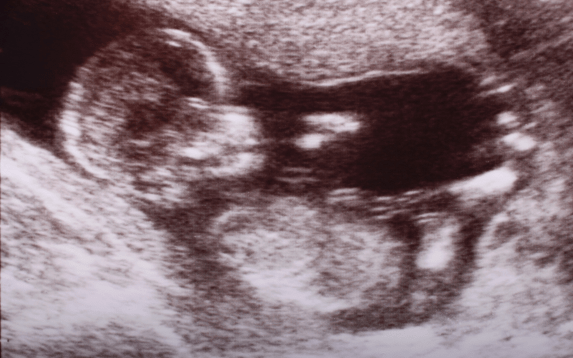

A Nuchal Translucency (NT) scan is an important ultrasound performed during early pregnancy, usually between 11 and 14 weeks. It helps assess the baby’s risk of certain chromosomal abnormalities, such as Down syndrome, Edwards syndrome, and Patau syndrome. The test measures the fluid-filled space at the back of the baby’s neck. A higher-than-normal reading may indicate a potential genetic concern.

The NT scan is a safe, non-invasive procedure that takes only a few minutes. During the scan, the sonographer gently moves the probe over your abdomen to capture detailed images of the fetus. The process is painless and does not harm you or your baby. At Isha IVF, our specialists use advanced imaging technology to ensure precise and clear results, providing both accuracy and comfort for the mother.

After the scan, the doctor will review the measurements of the nuchal translucency and discuss the findings with you. It’s important to understand that the NT scan is a screening test, not a diagnosis. A higher NT reading does not always mean the baby has a problem; it only indicates a possible risk. In such cases, your doctor may recommend further testing, such as Non-Invasive Prenatal Testing (NIPT) or diagnostic procedures like CVS or amniocentesis.